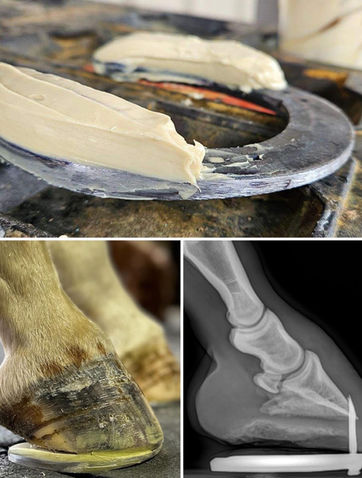

From performance horses to complex cases. Precision trimming, therapeutic shoeing, and innovative techniques designed to improve soundness, prevent injury, and support long-term hoof health.

Inspired by years of fabricating different shoes, devices, and packages to help horses heal and perform. The Adapter was created as a base shoe with multiple attachments to help with issues throughout the shoeing cycle.